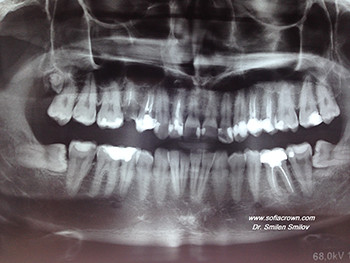

Екстрахирани два долни полуретенирани мъдреца. Екстрахиран е зъб 15 и поставен зъбен имплант Zimmer след 2 месеца, с цел запазване на меки тъкани поради отказ от страна на пациента за небцова съединително-тъканна присадка. Инициалната стабилност е ~60 nm., което позволи имедиатното натоварване на импланта. Снимката е направена 6 месеца след имплантацията, при която не се наблюдава крестална резорбция или такава в дълбочина.